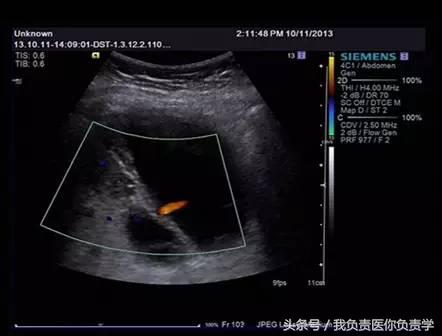

患者女,68岁,因上腹部痛 8天就诊 。超声检查发现胆囊体积明显增大,内部透声差,囊壁明显增厚,胆囊周围可见不规则分布的液性暗区。胆囊壁局部回声中断,探头加压及松开时,CDFI可见中断处出现因液体进出胆囊而导致的多普勒信号。患者行胆囊切除术,术后证实为胆囊穿孔。

图3-图6示胆囊壁局部回声中断,探头加压及松开时CDFI可见红色及蓝色多普勒信号